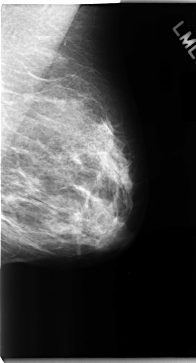

C_0091_1.LEFT_MLO

LEFT_MLO LINES 4712 PIXELS_PER_LINE 2544 BITS_PER_PIXEL 12 RESOLUTION 50 NON_OVERLAY